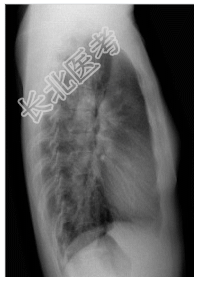

- [材料题] 患者,女性,25岁,发现心脏杂音24年,伴活动后气促1年余。查体.左侧第二肋间喷射性杂音,第二心音亢进,固定分裂。行胸部平片检查。

- 简答题1、诊断及依据是什么?

- 简答题2、鉴别诊断有哪些?